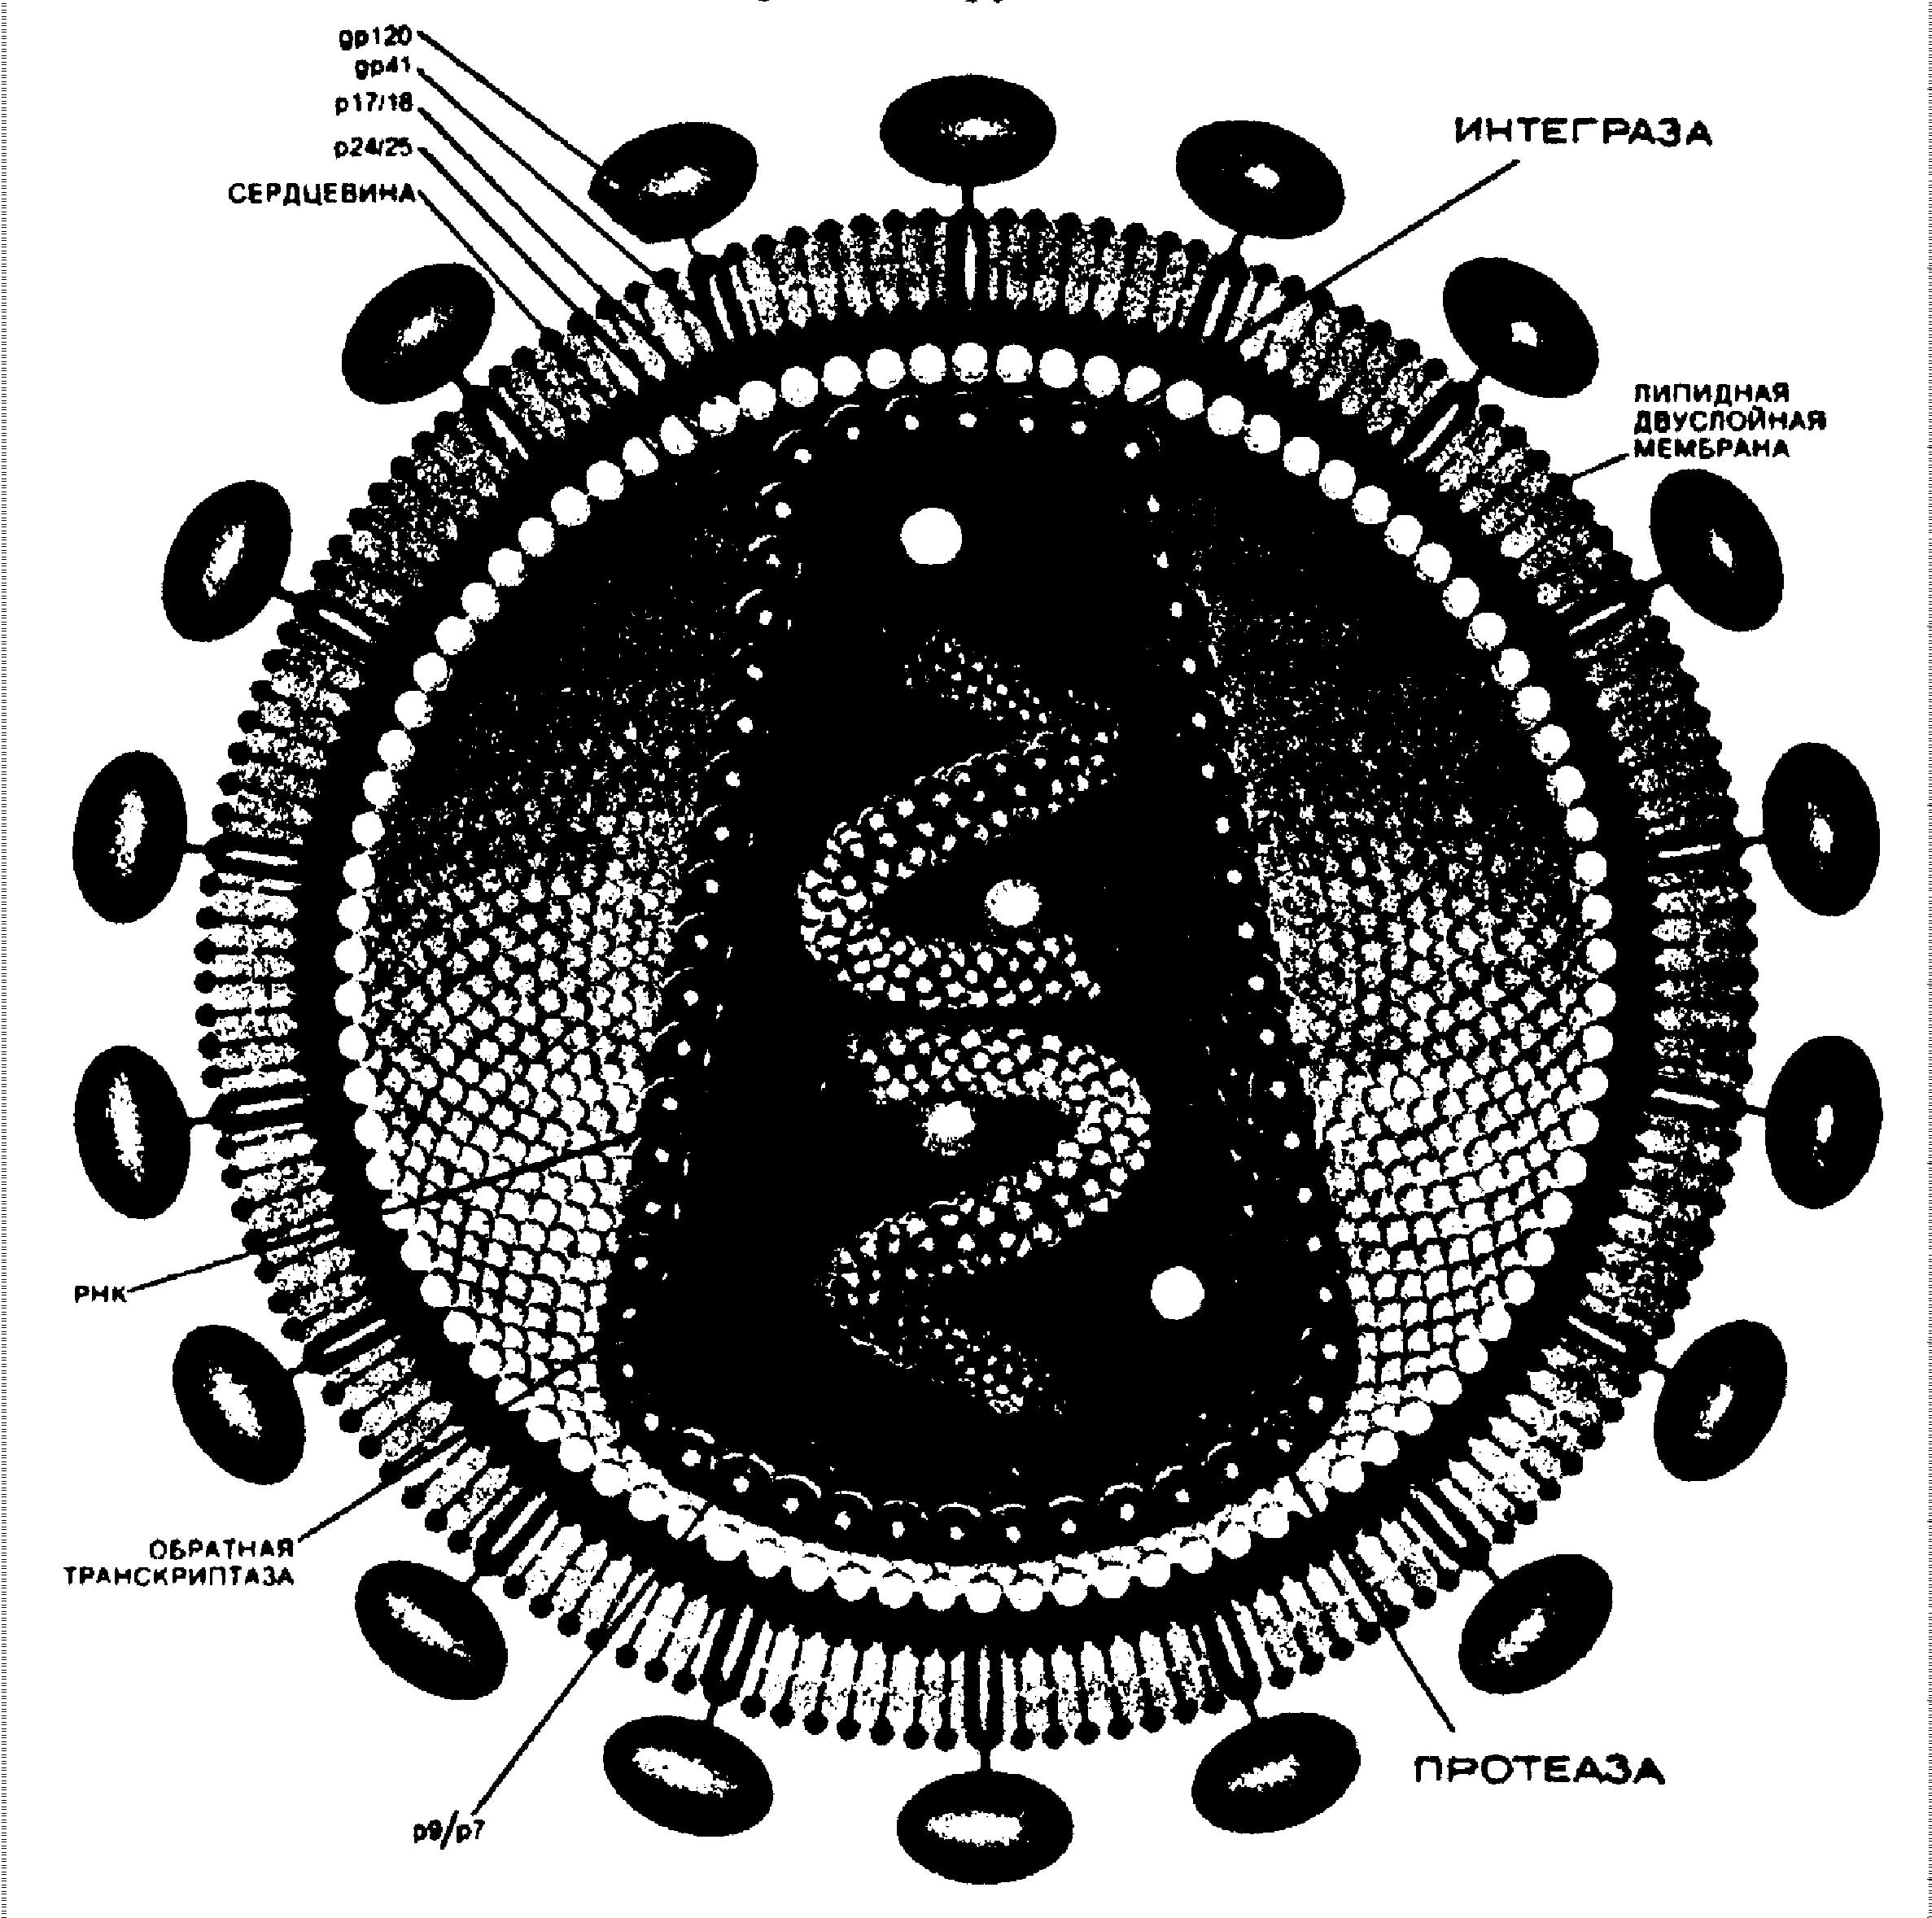

Рис 2. Строение вируса иммунодефицита человека в поперечном сечении. Антенны оболочки образованные белком gp120, связанным с белком gp41. Внутренняя оболочка вируса формируется белком p17/18.

Сердцевина вируса содержит белок р25 (или р24), РНК, несущую генетическую информацию и окруженную молекулами белка р9/р7, и ферменты – обратную транскриптазу, интегразу и протеазу. При участие обратной транскриптазы синтезируется провирусная ДНК, интеграза катализирует встраивание провирусной ДНК в хромосомную ДНК клетки и эта провирусная ДНК остается в латентном состоянии, пока клетка чем-нибудь не активируется. Тогда начинается продукция новой генерации вируса.